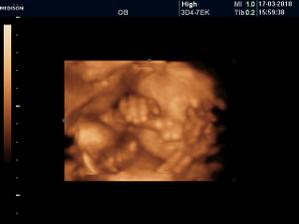

Vyrobene z velkej lasky